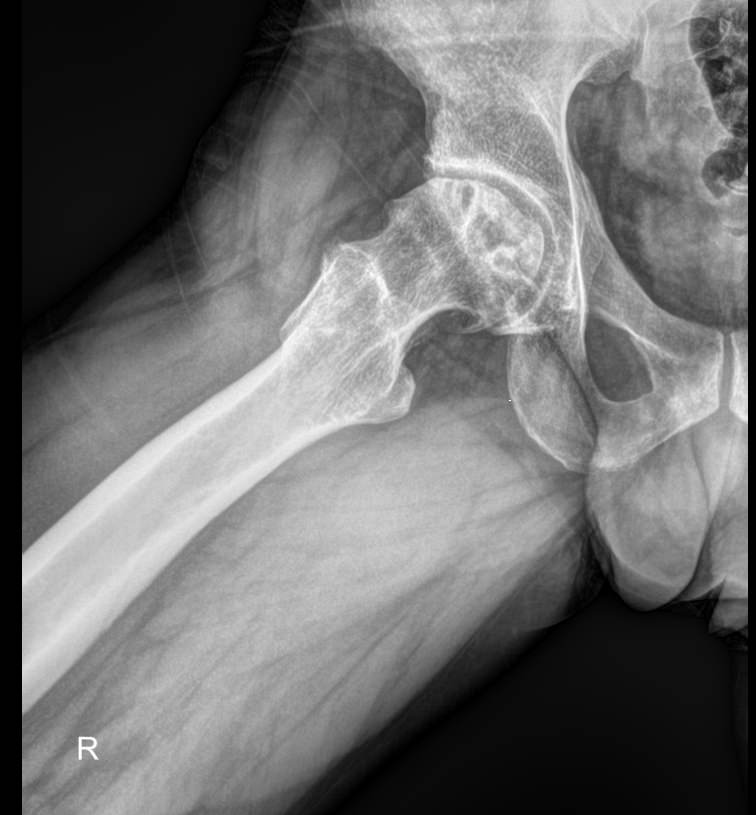

Рентгенография ― один из классических видов диагностики костей и суставов. Костная ткань, как наиболее плотная в организме, поглощает больше всего излучения и на стандартном негативном снимке выглядит самой светлой. При этом ясно видны все патологические изменения: разрежение и новообразования костей, утолщение или расслоение надкостницы, вывихи и переломы.

На рентгене можно обнаружить такие элементы тазобедренного сустава:

• Вертлужная впадина, сформированная из подвздошной, седалищной и лонной костей;

• Головка, шейка и другие образования бедренной кости;

• Суставная щель.

Их изменения говорят об острой или хронической патологии данной области.

В протоколе подробно описывают:

• Состояние мягких тканей ― в норме или есть признаки изменений;

• Суставную щель ― ширина нормальная или измененная, равномерно или нет, затенена или обычая, есть ли краевые костные разрастания или обломки кости;

• Конгруэнтность/соответствие головки и впадины ― норма, вывих, подвывих;

• Структуру кости, надкостницы ― обычные или патологические;

• Новообразования, если есть ― их размеры и локализацию.